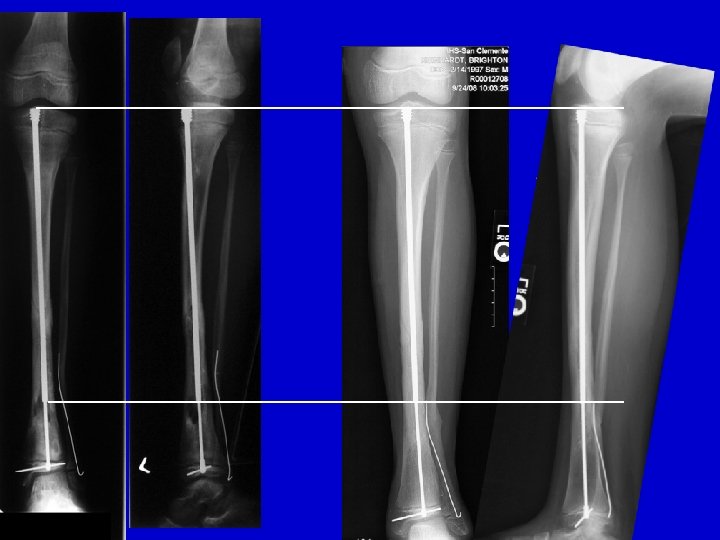

Treatment Type III • Closed distraction • Gradual deformity correction • ± Lengthening • ± IM Rod (late)

distraction of CPT follow-up

RESULTS Periosteal & Bone Grafting with IM rod and Ilizarov 1997 -2008 20 patients treated Union: 20/20